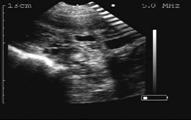

19 days of gestation

21 days of gestation

22 days of gestation